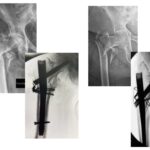

(εικόνα 8, δύο παραδείγματα υπερηλίκων ασθενών που εξαιτίας της μεγάλης συντριβής δεν επετέυχθη κλειστή ανάταξη. Ήταν αναγκαίο λοιπόν να τοποθετηθούν οστικά “σύρματα” με σκοπό να συκρατηθούν τα οστικά τεμάχια: μια τεχνική απαιτητική που απαιτεί μεγάλη εμπειρία)